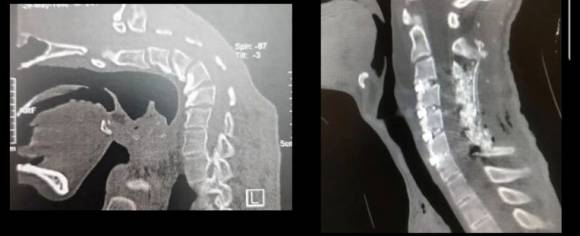

의료진은 정신과 치료와 함께 꺾인 목뼈를 바로 세우는 수술을 병행했다. 목뼈와 근육 일부를 제거하고, 나사와 막대 등으로 흐트러진 균형을 바로잡는 교정 방식을 활용했다.

수술은 성공적이었고 다음날부터 정상 보행한 환자는 3일 후 퇴원했다. 1년의 추적 관찰에서도 목뼈 정렬과 교정이 만족스럽게 개선된 것으로 확인됐다.